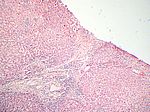

Aktive aggressive chronische Hepatitis, HE